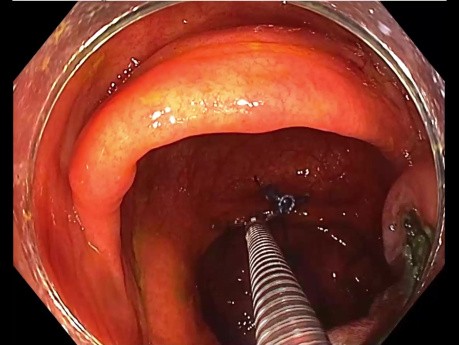

Méthode de Traction du Côlon Droit pour LST (Tumeur...

Cas d'endoscopie chirurgicale : méthode de traction lors de la dissection sous-muqueuse endoscopique (DSE) pour LST du côlon droit.